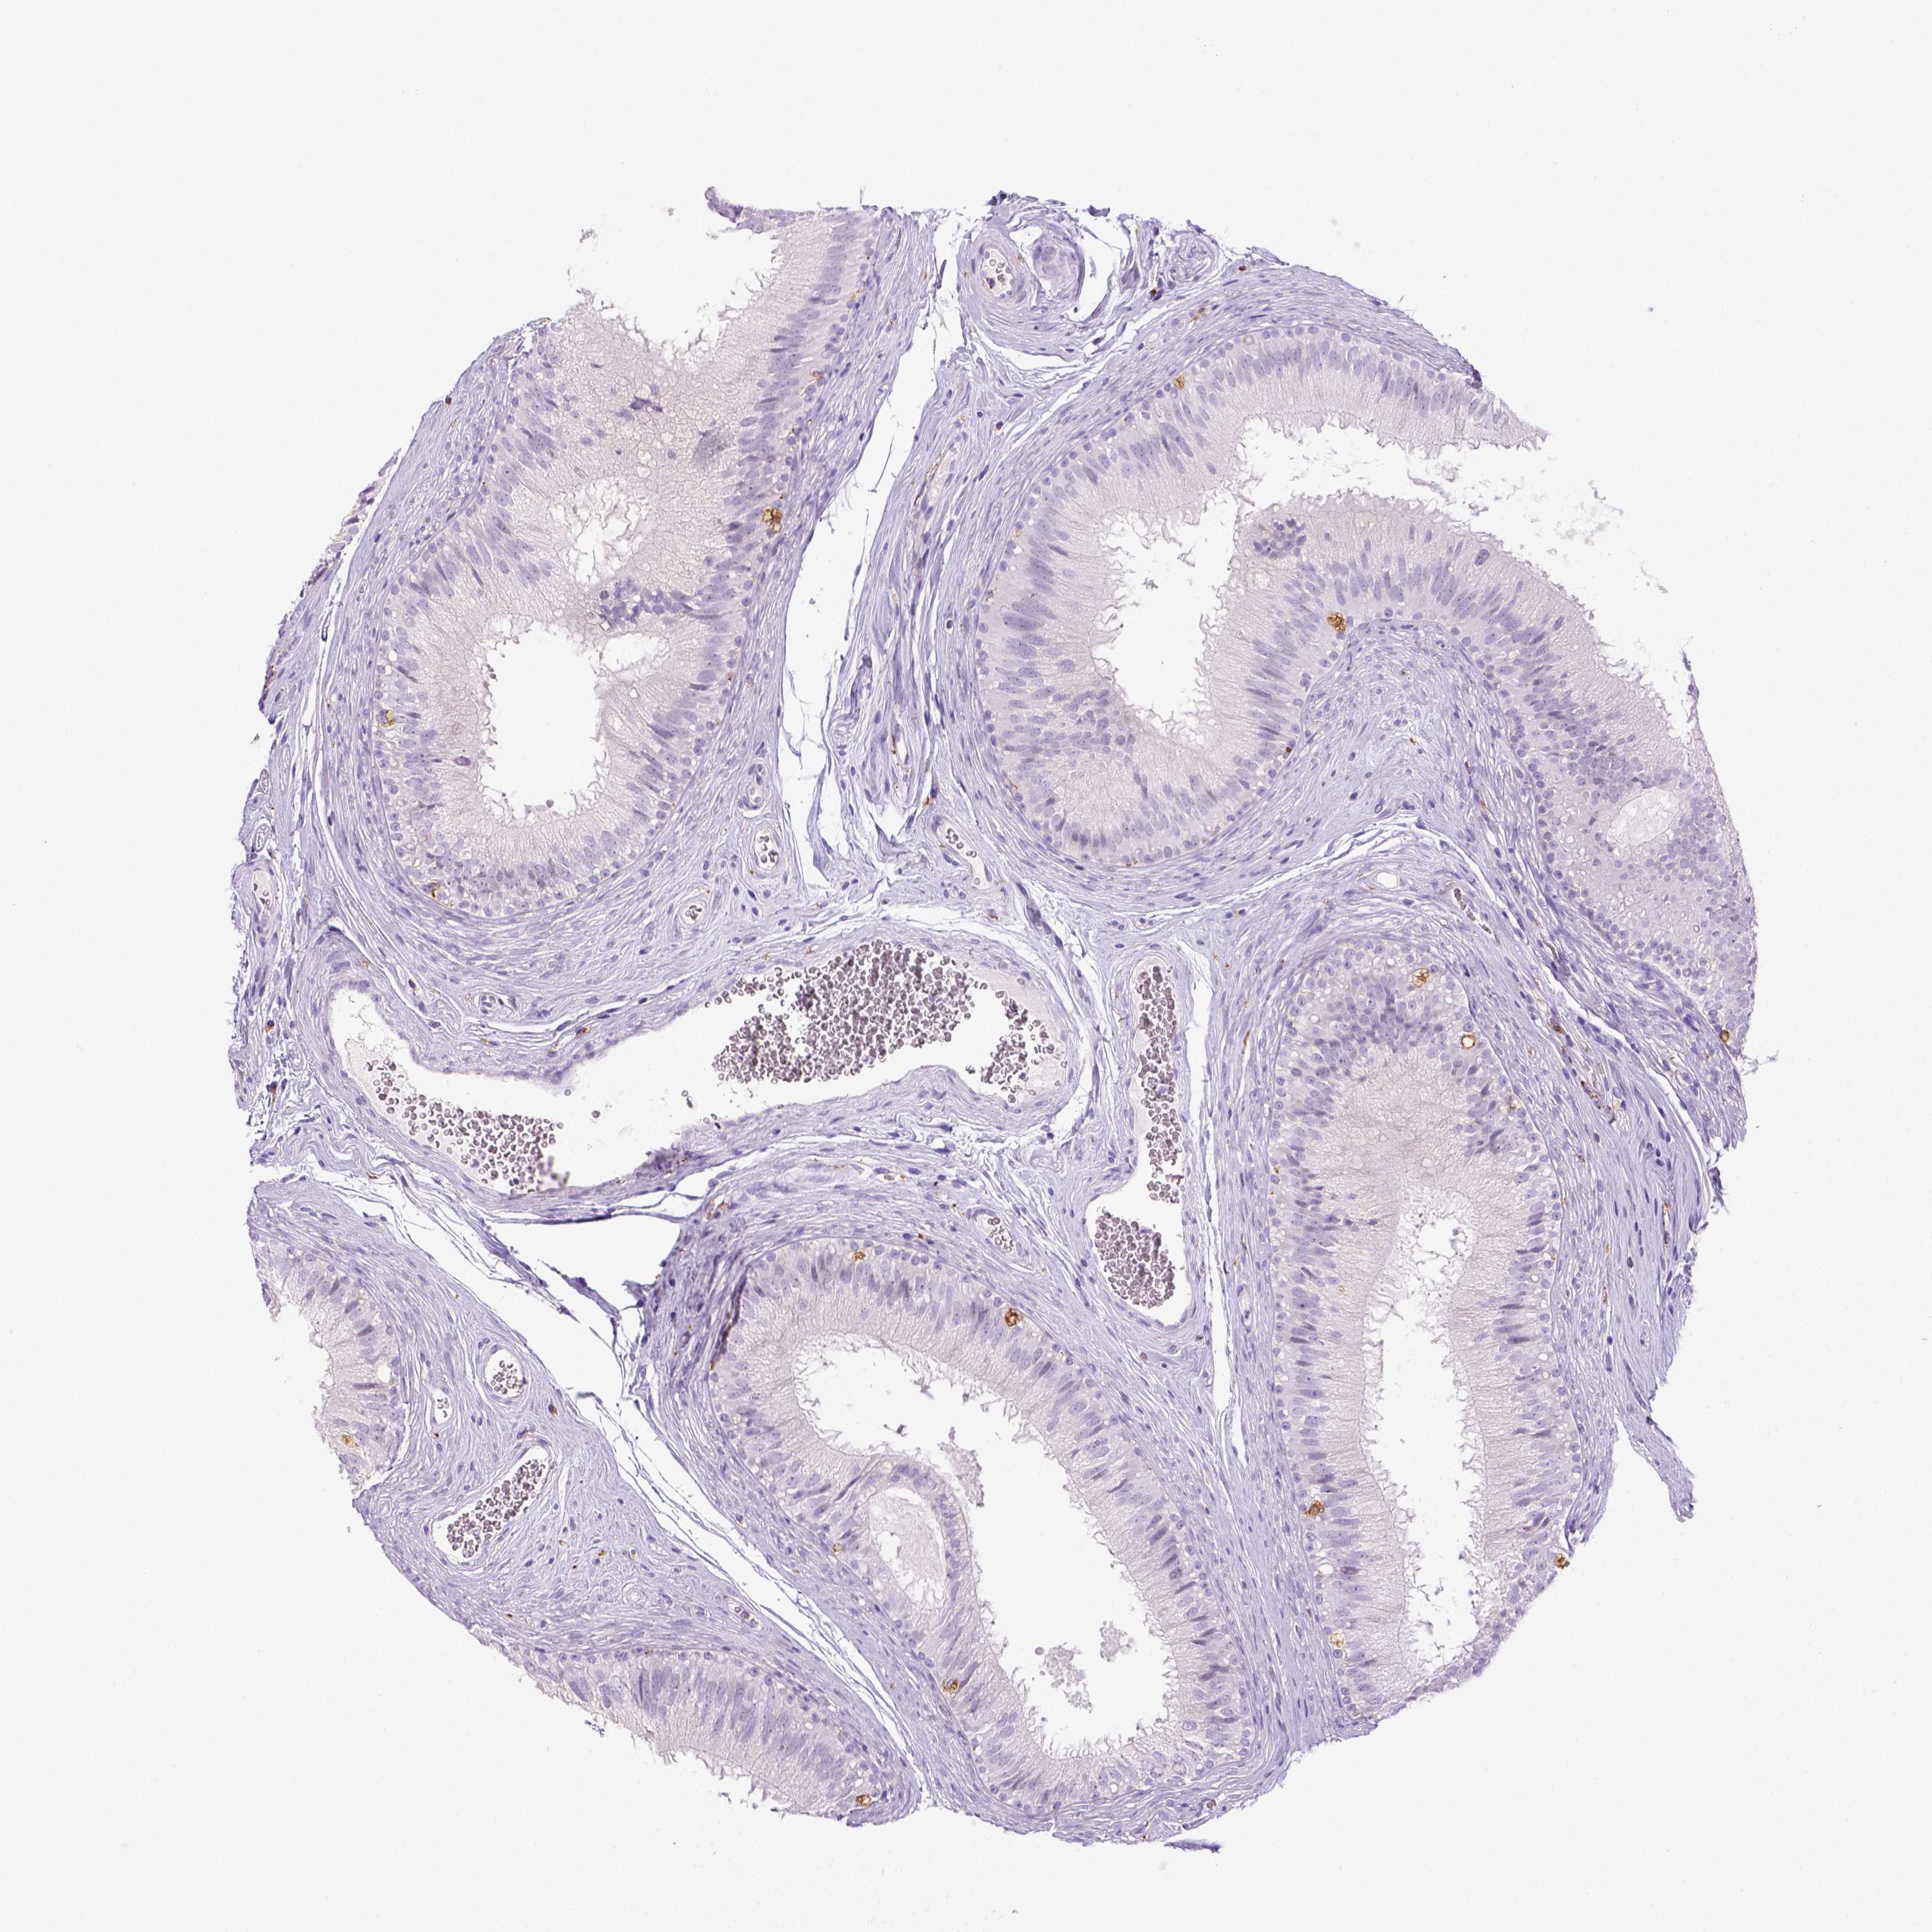

TISSUE PRIMARY DATA EPIDIDYMIS Show tissue menu

EPIDIDYMIS - Antibody stainingi

Antibody staining in the annotated cell types in the current human tissue is reported as not detected, low, medium, or high, based on conventional immunohistochemistry profiling in selected tissues. This score is based on the combination of the staining intensity and fraction of stained cells.

Each image is clickable and will lead to virtual microscopy that enables deeper exploration of all samples and also displays staining intensity scores, fraction scores and subcellular localization as well as patient and tissue information for each sample.

Antibody HPA048982Antibody CAB000051Antibody CAB000066Antibody CAB072861Antibody CAB072862

Glandular cells Not detectedNot detectedNot detectedNot detectedNot detected